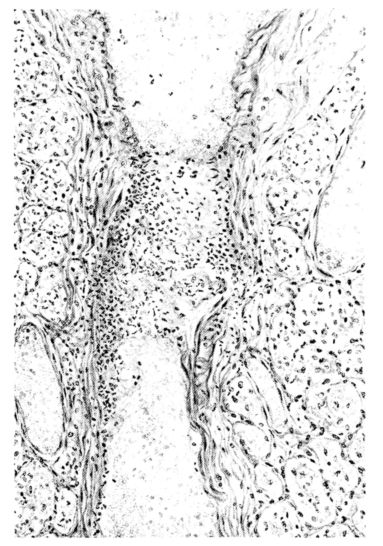

FIG. III. AUTOPSY NO. 90. DRAWING FROM A LESION OF THE TRACHEA (SOMEWHAT OLDER THAN THAT ILLUSTRATED IN FIGURE II). THE MUCOSA IS ENTIRELY LACKING. CONGESTION AND EDEMA ARE THE STRIKING FEATURES IN THE SUBMUCOSA. THE NECROTIZING PROCESS HAS EXTENDED INTO THE MUCUS GLANDS. THIS IS SHOWN IN THE LOWER PICTURE.

The changes are less marked, perhaps, in the trachea than in its finer ramifications. The mucosa is constantly more or less destroyed and large areas, usually focal, are entirely devoid of their epithelial covering. This is replaced by a sparse exudate, composed largely of red blood cells, mucus, a small amount of fibrin, and nuclear fragments (Fig. II). It may dip into the submucosa for a short distance, but usually these indentures are associated with the ducts of the mucous glands into which the inflammatory reaction extends. A more striking feature than the exudate, however, is the edema and the congestion of the submucosa. The loose areolar tissue of the submucosa is spread widely apart, and throughout it distended blood vessels are very conspicuous. Occasionally such a vessel is broken and actual hemorrhage appears in the submucosa. Occasionally, too, the inflammation extends down the duct to the mucous gland itself, and here, also, aplastic inflammatory reaction is evident, inasmuch as the acini now stain intensely red with the cells undifferentiated from each other and specked here and there by broken remains of the dead nuclei (Fig. III). After the disease has continued for a short period, even at the end of five or six days, some regeneration of the epithelial lining may be seen (3) (Fig. IV). But despite this, the acute picture persists, and there goes on, side by side, an attempted repair characterized by epithelial regeneration and the same evidence of acute change. Since the lesion is essentially a superficial one, scars or contractures of any extent are not encountered in the trachea, even in examples of the disease that have ended fatally only after many weeks.[4]

15There is considerable evidence to support the view that the disease spreads from bronchus to bronchus, and in keeping with this view, various stages in the inflammatory processes are more readily determined in these smaller structures than in the trachea. Furthermore, it must be emphasized that even the mildest and the most extreme of these stages are not infrequently encountered in the same lung. The earliest lesion is manifested by an increased homogeneity of the protoplasm of the epithelial lining of the bronchus. The cell protoplasm loses its normal granulation and the nucleus, somewhat darker than usual, becomes conspicuous on a red base (Fig. V). In the lumen of such a tube a serous exudate, perhaps mixed with mucus, is encountered, and there is some spreading apart of the surrounding muscular tissue with engorgement of the vessels. This picture merges gradually into one where the epithelium appears as a homogeneous, red-staining ribbon, devoid of nuclei, often exfoliated, in part at least, from the underlying submucosa (92). The change is traceable through the larger bronchi, even to the ducti alveolares, and not infrequently, bacteria, either as a diffuse, minute dotting or in the form of circumscribed, colony-like formations, are spread through the red, ribbon-like strand (Fig. XVI). With the exfoliation of the epithelial lining, the submucous vessels become more and more conspicuous and may bulge into the lumen of the tube (Fig. VI). That they actually weep into the lumen is proved by the presence of red blood cells in the exudate, now rich in mucus, broken-down nuclei, and desquamated cells. The necrotizing process may not extend deeper than the epithelial lining as is the status described above (140, 162), but it also frequently involves the underlying submucous and muscular layers, so that these lose their identity and stand out as homogeneous masses, in which fragmented nuclei and bacterial accumulations are prominent. Such deeper necrotizing areas may be focal (Fig. VII), or may involve the entire circumference of the tube (Fig. VIII). Occasionally, the epithelium, now dead and staining homogeneously, is lifted from the underlying submucosa in the form of a blister (66), and has very much the same appearance as the well known, early reaction which follows the application of croton oil to the rabbit’s ear. Where this occurs, the submucosa is less involved, as though the necrotizing agent had not penetrated to the same depth and the serous reaction beneath were actually a beneficent exudate. These blisters are in contrast with the deeper areas where the fibrinous mass, mixed with the dead tissue, forms an intensely staining ring or band, which extends through the bronchiolar wall even to the surrounding alveoli.